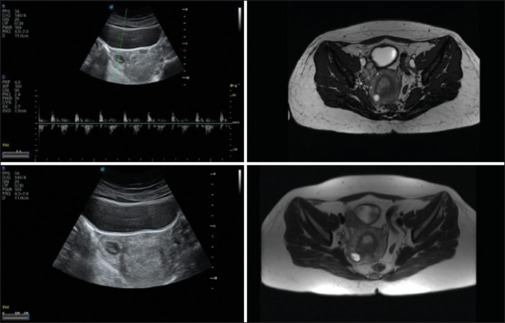

Interstitial pregnancy accounts for only 2%-4% of all ectopic pregnancies, however, it is associated with higher mortality rates as compared to other ectopic pregnancies, due to the associated risk of uterine rupture, and hemorrhage. A 35-year-old gravida 4 abortion 3 woman reported at the 8th week of gestation for antenatal care with comorbidity of protein C and protein S deficiency and recurrent pregnancy loss with for routine care. She was diagnosed as a case of interstitial pregnancy by transvaginal sonography and magnetic resonance imaging. She was subsequently managed by laparoscopic cornuostomy. Prompt recognition and definitive management are crucial in averting life-threatening hemorrhage due to this rare condition.